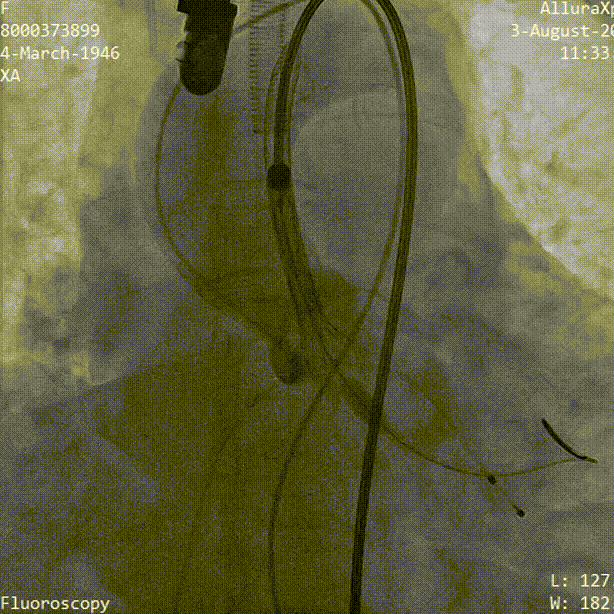

术中影像

导丝顺利跨瓣

TaurusAtlas 20mm球囊充分预扩张,无明显腰征 无漏

TaurusElite输送器顺利过弓

TaurusElite AV23瓣膜初始定位

瓣膜逐步释放至工作位过程

工作位造影 瓣膜位置良好

冠脉灌注良好